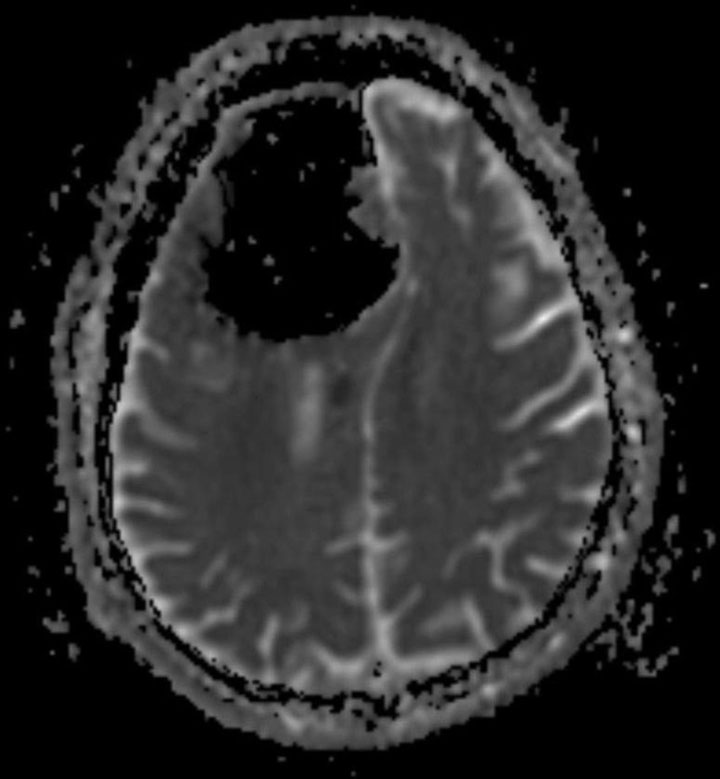

MRI showing area of acute infarction, or stroke. BMJ Case Reports 2018

As more air got in, it slowly pushed the brain aside, said Brown. It pushed and compressed the brain, a soft organ, to make room for the air. And as this happened, doctors believe the pressure may have caused a small stroke due to lack of blood flow to that part of the brain.